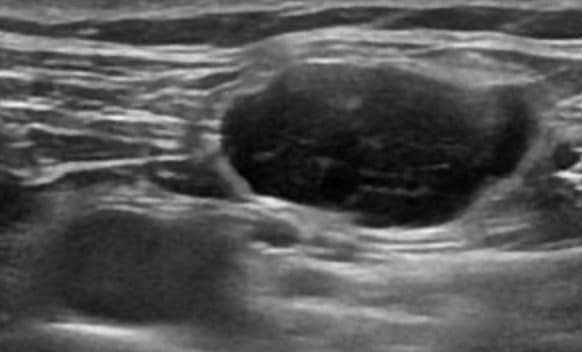

초음파 검사만으로는 악성 연조직종양을 진단할 수 없다. 그렇지만, 연조직 종괴가 인접한 관절과 분리되고, 내부의 괴사, 불규칙한 혈관 등을 가질 때 악성을 의심해 볼 수 있다. 연조직육종(soft tissue sarcoma)은 보통은 약간 낮은 에코를 보이나, 높은 에코, 과혈관성, 내부의 괴사에 의한 낮은 에코나 에코 없음을 보일 수 있다. 림프종(lymphoma)은 다양한 에코를 보이나, 주로 낮은 에코의 종괴로 나타나며, 메아리투과증가(through-transmission)에 의해서 깊은 부위가 밝게 보일 수 있다. 환자의 나이와 림프가 있을 위치에서 발견될 때 진단 가능하기도 하지만, 대부분은 경피적 조직검사가 필요하다.

림프종 초음파 영상 초음파유도하생검을 하면 인접한 혈관과 종괴 안의 괴사 부위를 피해서 바늘의 끝을 정확하게 종괴의 고형 부분에 위치시킬 수 있으므로 진단정확도를 높일 수 있다. 악성질환의 연조직 전이는 과혈관성의 다양한 에코의 종괴로 보인다. 초음파검사는 연조직 악성질환 치료 후 경과 관찰에서 연조직에 재발한 종괴를 찾는데도 이용된다.

임상적으로 찾아지기 전에 흑생종(melanoma)이나 전이(metastasis)가 초음파검사에서 찾아지기도 한다. 연조직 육종의 재발을 찾는데 초음파검사가 MRI 검사만큼 효과적이라는 보고도 있다. 연조직종양에 인접한 뼈의 이상이 보일 때 뼈의 침범 가능성을 의심할 수 있고 또는 원발성 악성 뼈종양이거나 뼈에 전이한 종양이 연부조직으로 퍼진(extension)것일 수도 있다.